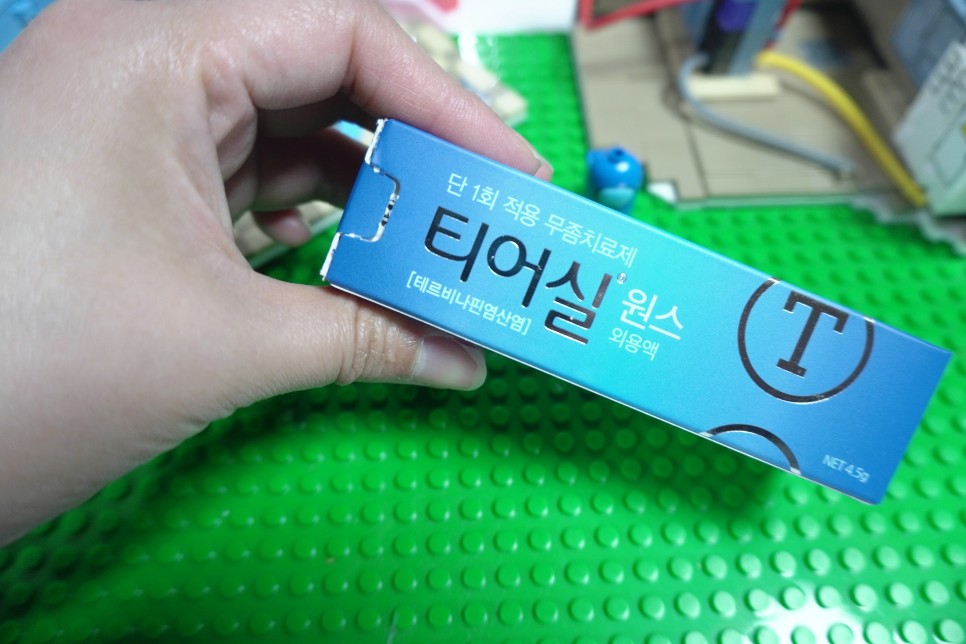

단 1회의 도포만으로 빠른 효과를 얻을 수 있다고 적혀 있습니다!지금부터 시작하자는 단계이므로, 이번만 바르는 것으로 올해는 무좀 없이 지나갔으면 합니다.

티어씰 원스가 단 한번의 사용으로 효과를 볼 수 있는 것은 자체 특허를 출원한 실리콘 필름막 기술 덕분입니다.약을 바르면 실리콘 필름이 형성되어서 오랫동안 무좀균을 살균해서 치료해준다고 하네요.한번 바르면 13일간 약효가 지속된다고 합니다.

매년 무좀이 재발하는 이유는 잘 낫지 않았기 때문이라고 하는데요.왜 끝까지 깨끗하게 치료하지 못했을까요?그건 아마 매일 약을 발라야 하는데 까먹어서.. 좀 괜찮아지니까 귀찮아서 안 발라서 그래요 티어실 원스는 한번만 발라도 약효가 13일 동안 지속되기 때문에 게으르고 잘 잊어버리는 사람도 끝까지 치료할 수 있을 것 같아요

티어씰 원스 무좀약 바르는 법1. 손발을 깨끗이 씻고 건조시킵니다.2. 발에 충분히 발라줍니다.3. 손을 깨끗이 씻으세요.4. 약 도포 후 24시간 동안 발을 씻지 말고 그대로 유지하세요!

한 병을 한꺼번에 다 쓴다구요! 충분히 한통을 양 다리에 바른후 남은거 무좀부위에 한번 더 바르시면 되요~